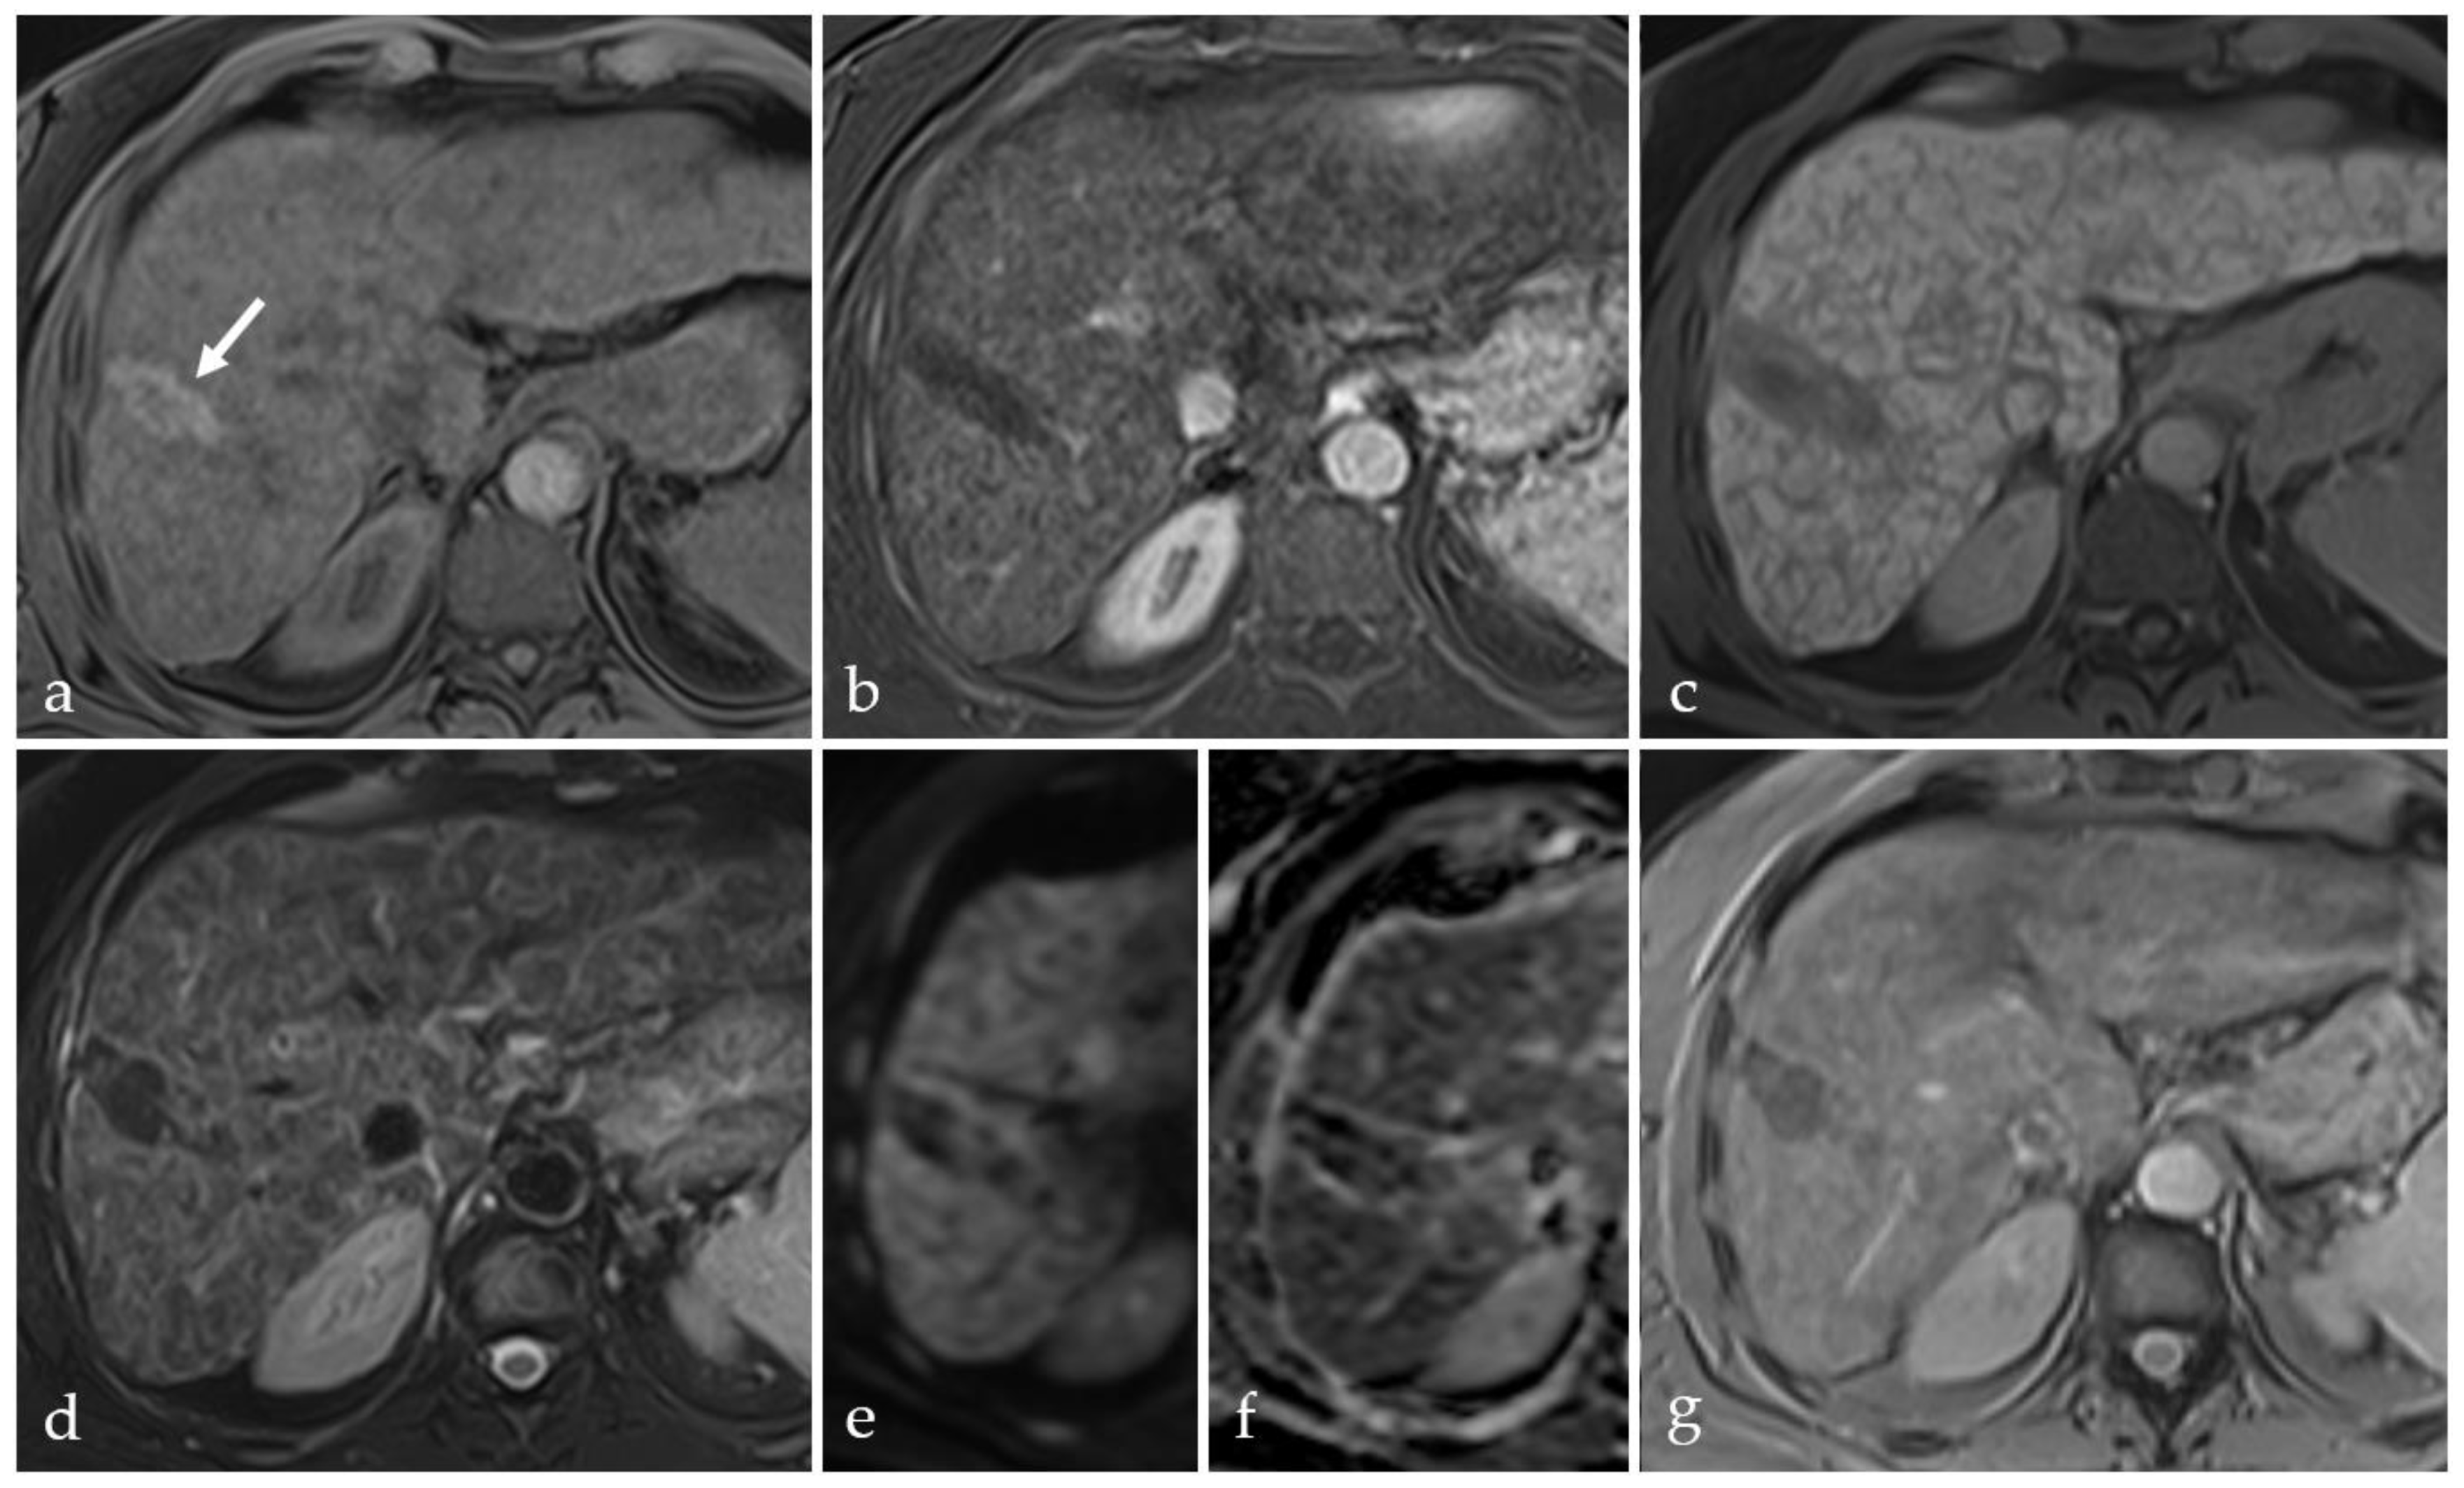

3.2. Expected Post-Treatment Imaging Features in the Absence of Viable Tumor Tissue

3.5. Post-Treatment Imaging Features of Tumor Viability